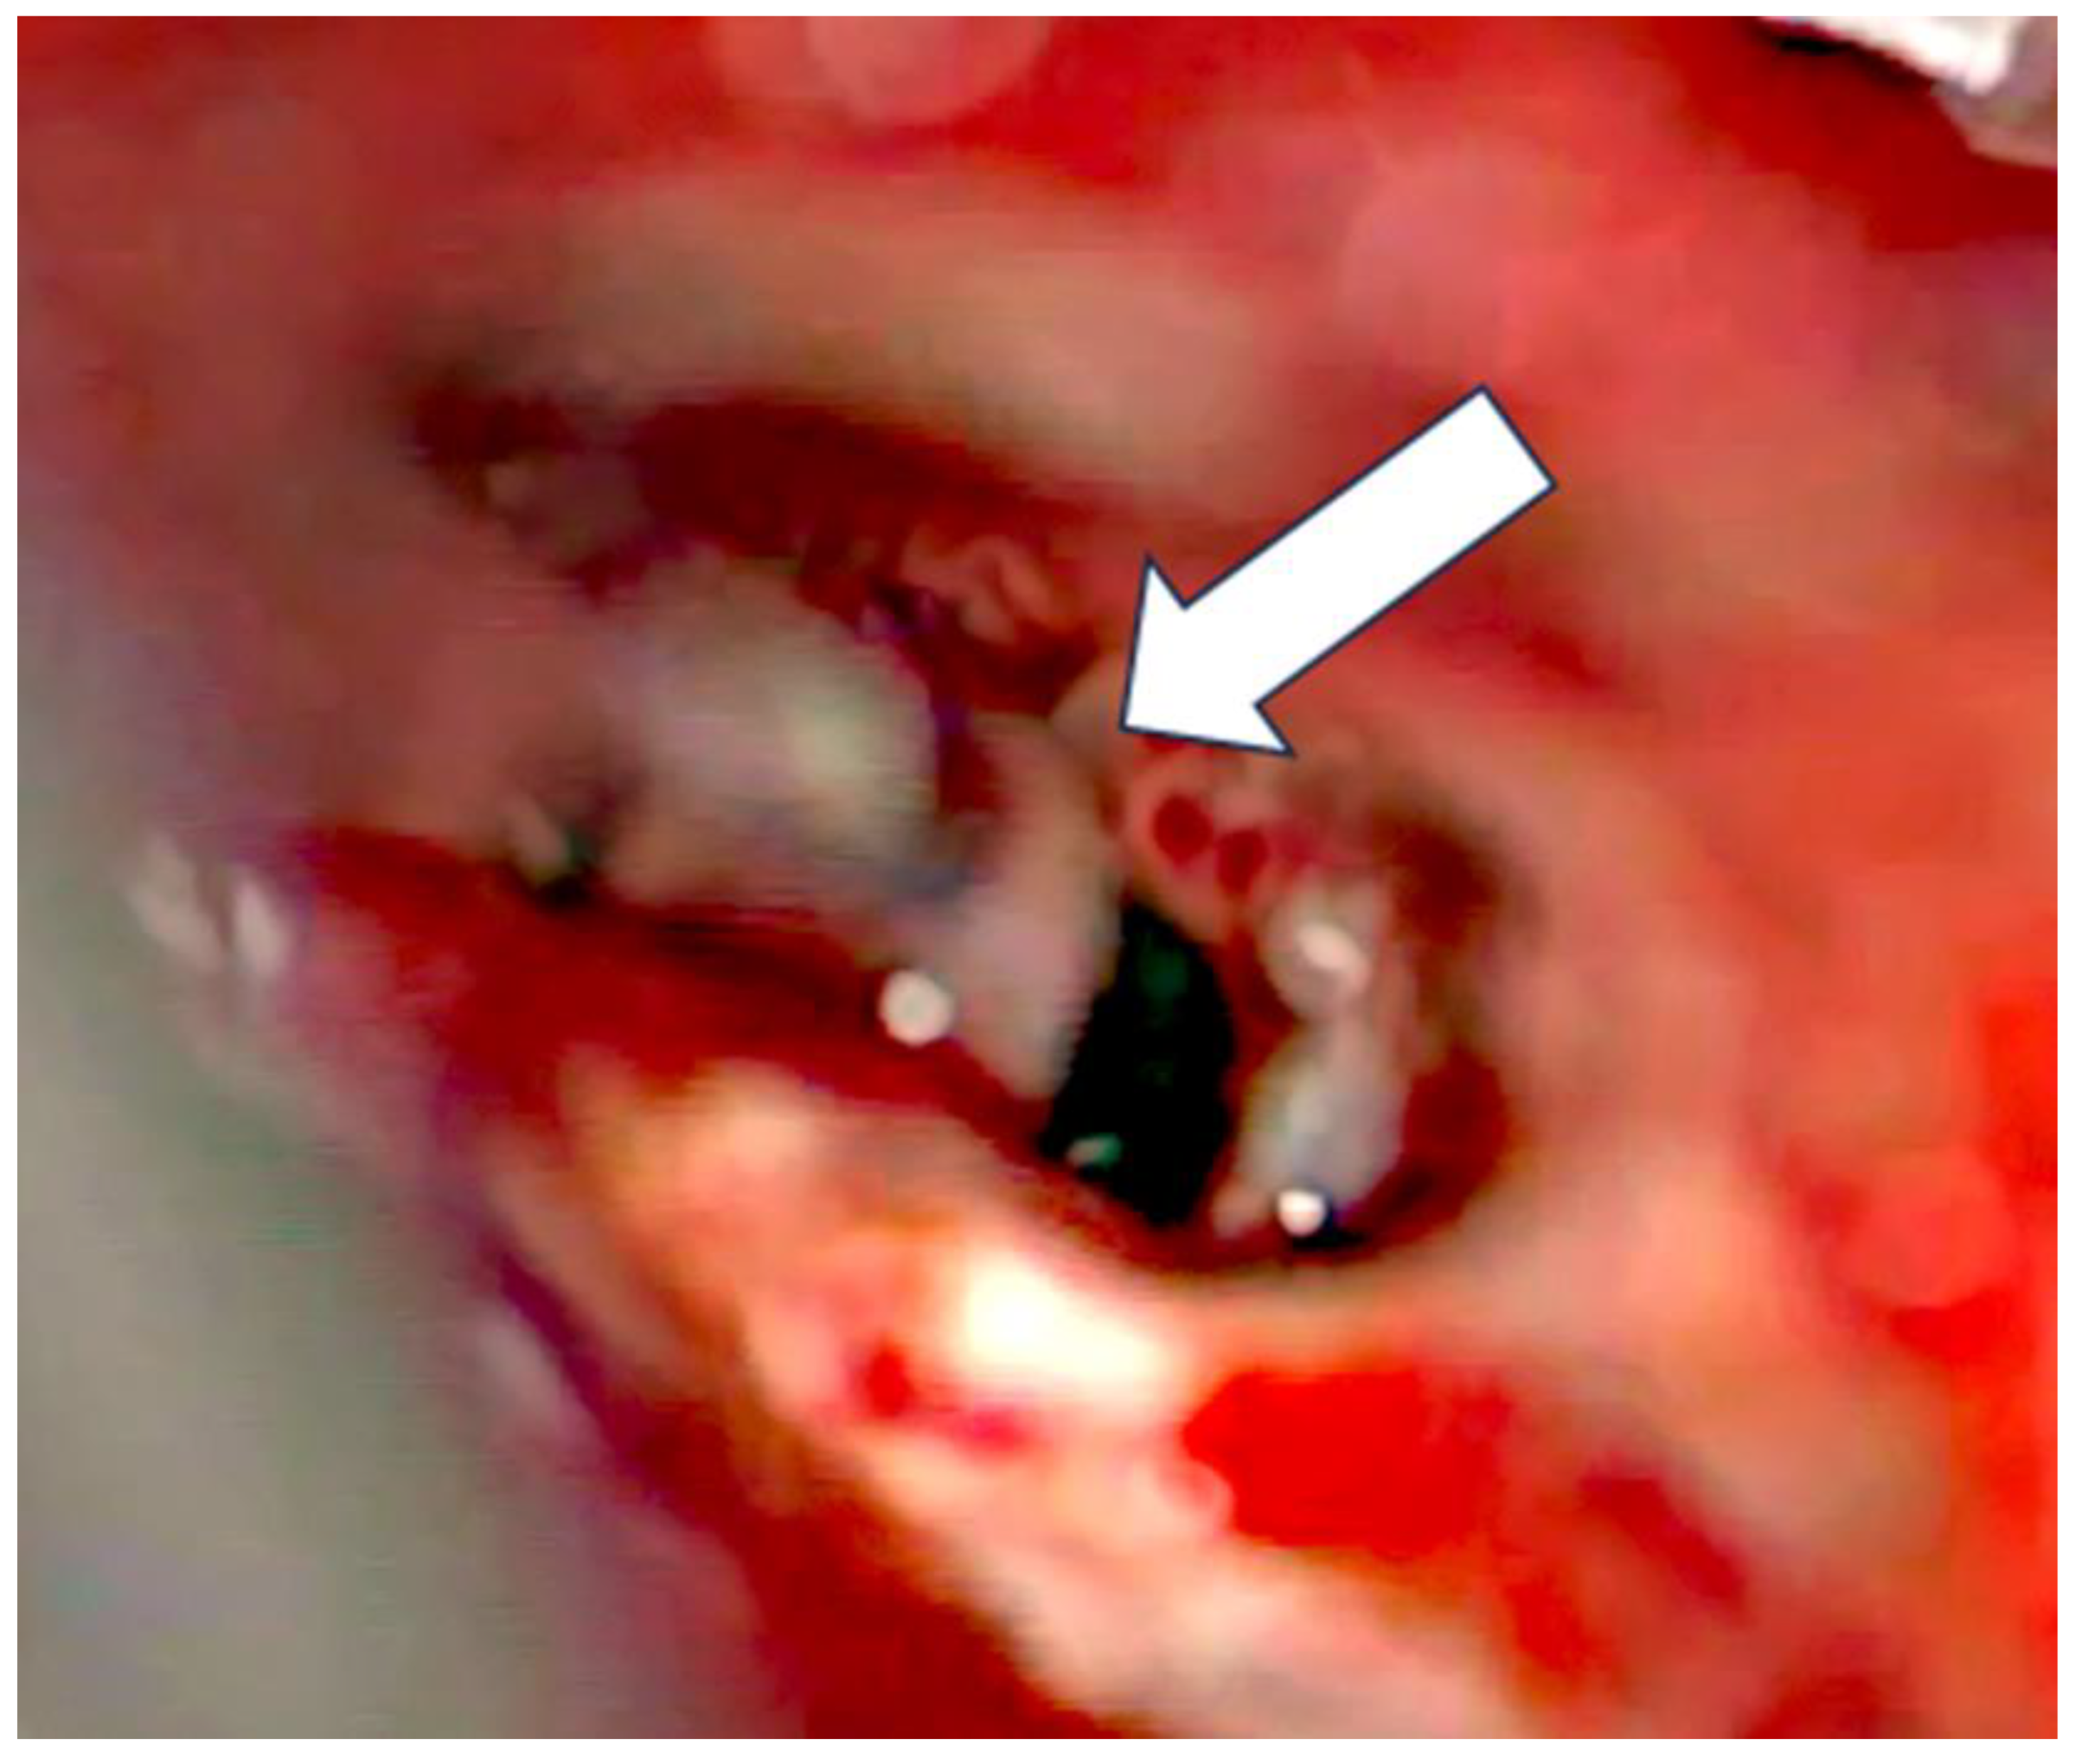

After the removal of parts of the tumor through the enlarged cochleostomy (Figure 1) the TRD was introduced (Figure 2) until the tip was visualized (Figure 3) and carefully grabbed out of the second turn access. By grabbing the tip, the device slipped into the cochleostomy and pushed parts of the tumor out of the second turn. Residual tumor parts could be detached by pipe cleaner handling (Figure 4) and sucked out (Figure 5).

Figure 3. Tip visualized in the second turn (arrow).

Figure 5. Removal of tumor parts (arrow).